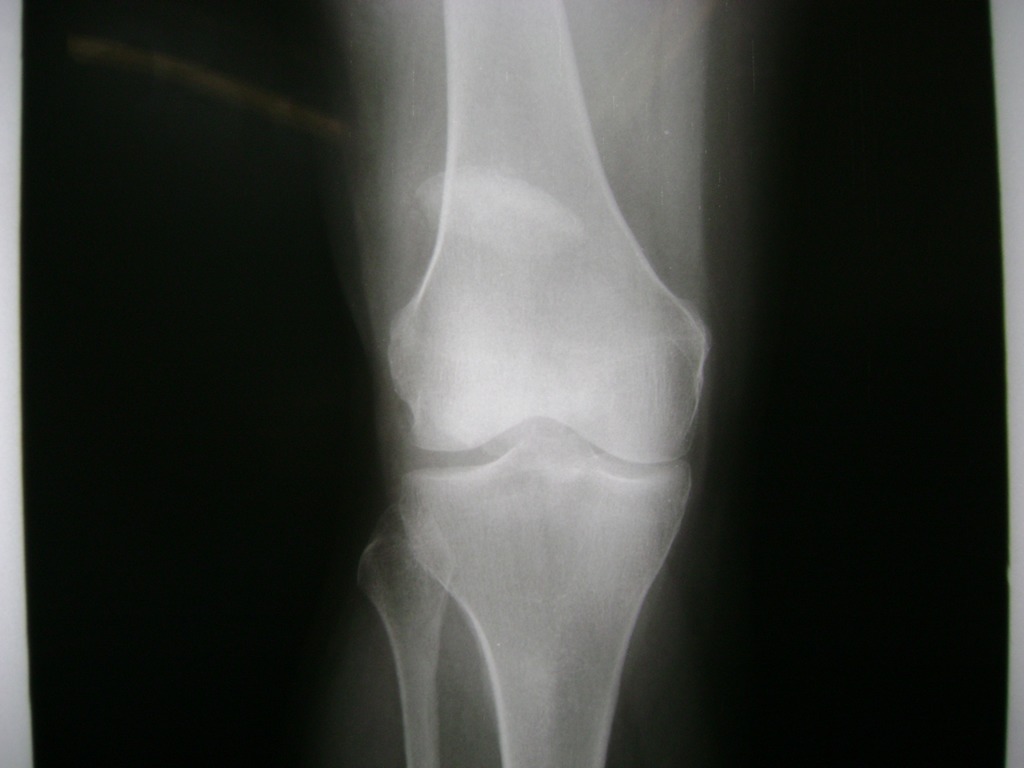

La artroscopia de rodilla es un cirugía en el cual la estructura interna de la articulación es examinada ya sea para realizar un diagnostico o para realizar un tratamiento, este procedimiento se realiza utilizando un instrumento parecido a un pequeño tubo llamado artroscopio.

La artroscopia se popularizo en 1960 y hoy en día es muy común en todo el mundo. Típicamente, es realizada por cirujanos ortopédicos de manera ambulatoria. Cuando se realiza de manera ambulatoria los pacientes pueden regresar a casa después de la operación, no se requiere quedarse en hospital.